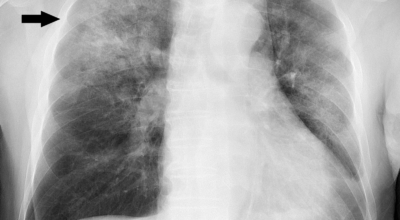

증상을 겪는 경우 배양 검사는 물론 X-ray 촬영 등을 통해 진단을 할 수 있어요. 필요한 경우 소변, 혈액, 혈청 검사, CT 등이 추가적으로 진행돼요.